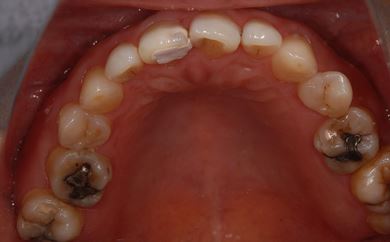

インプラントの症例写真 IMPLANT

インプラント治療+セラミック治療

| 主訴 | 前歯や、下の奥など、何本か気になる歯がある。 | ||||||||||||||||||||||||||||||||

| 治療方針 | インプラント治療により、機能的・審美的回復を行う。 | ||||||||||||||||||||||||||||||||

| 治療内容 | インプラント2本、メタルボンドセラミッククラウン4本、ジルコニアフレームオールセラミッククラウン1本(オールセラミック用土台1本) | ||||||||||||||||||||||||||||||||